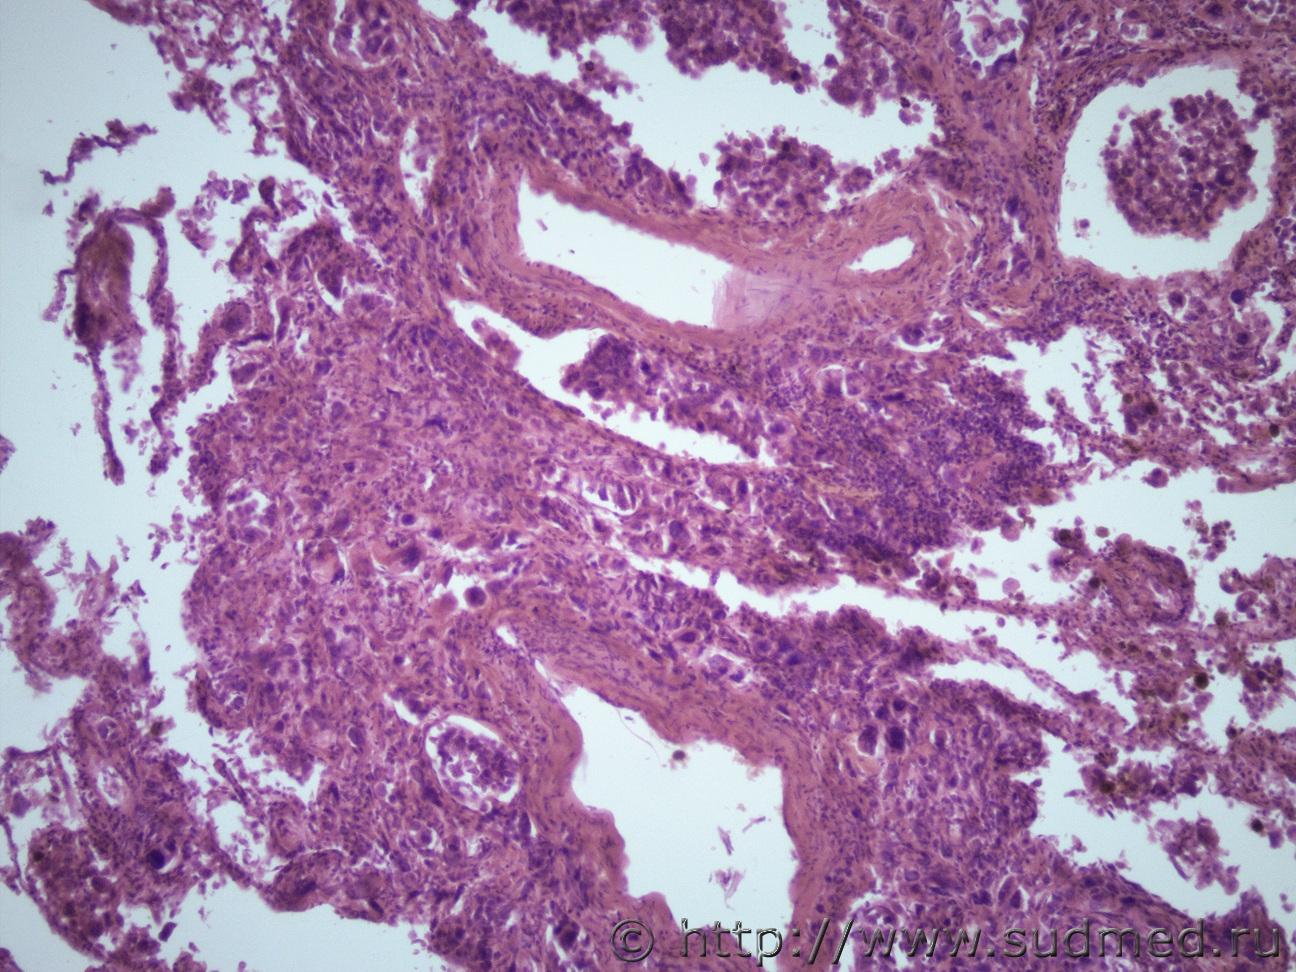

Ув. коллеги я как всегда к Вам с опухолью))). Муж 70 лет. Новообразование глотки справа с прорастанием в прилежащие мягкие ткани шеи, множественные метастазы в правое легкое, печень, подчелюстные и шейные лимфатические узлы.Судебная медицина - Прикрепленное изображение Судебная медицина - Прикрепленное изображениеСудебная медицина - Прикрепленное изображениеСудебная медицина - Прикрепленное изображениеСудебная медицина - Прикрепленное изображение

Судебная медицина - Прикрепленное изображениеСудебная медицина - Прикрепленное изображение Последние 3 легкие.

Аденокарцинома.

Похоже на mts ацинарноклеточной карциномы из легких. Многослойная плоскоклеточная структура вроде интактна, где глотка😏